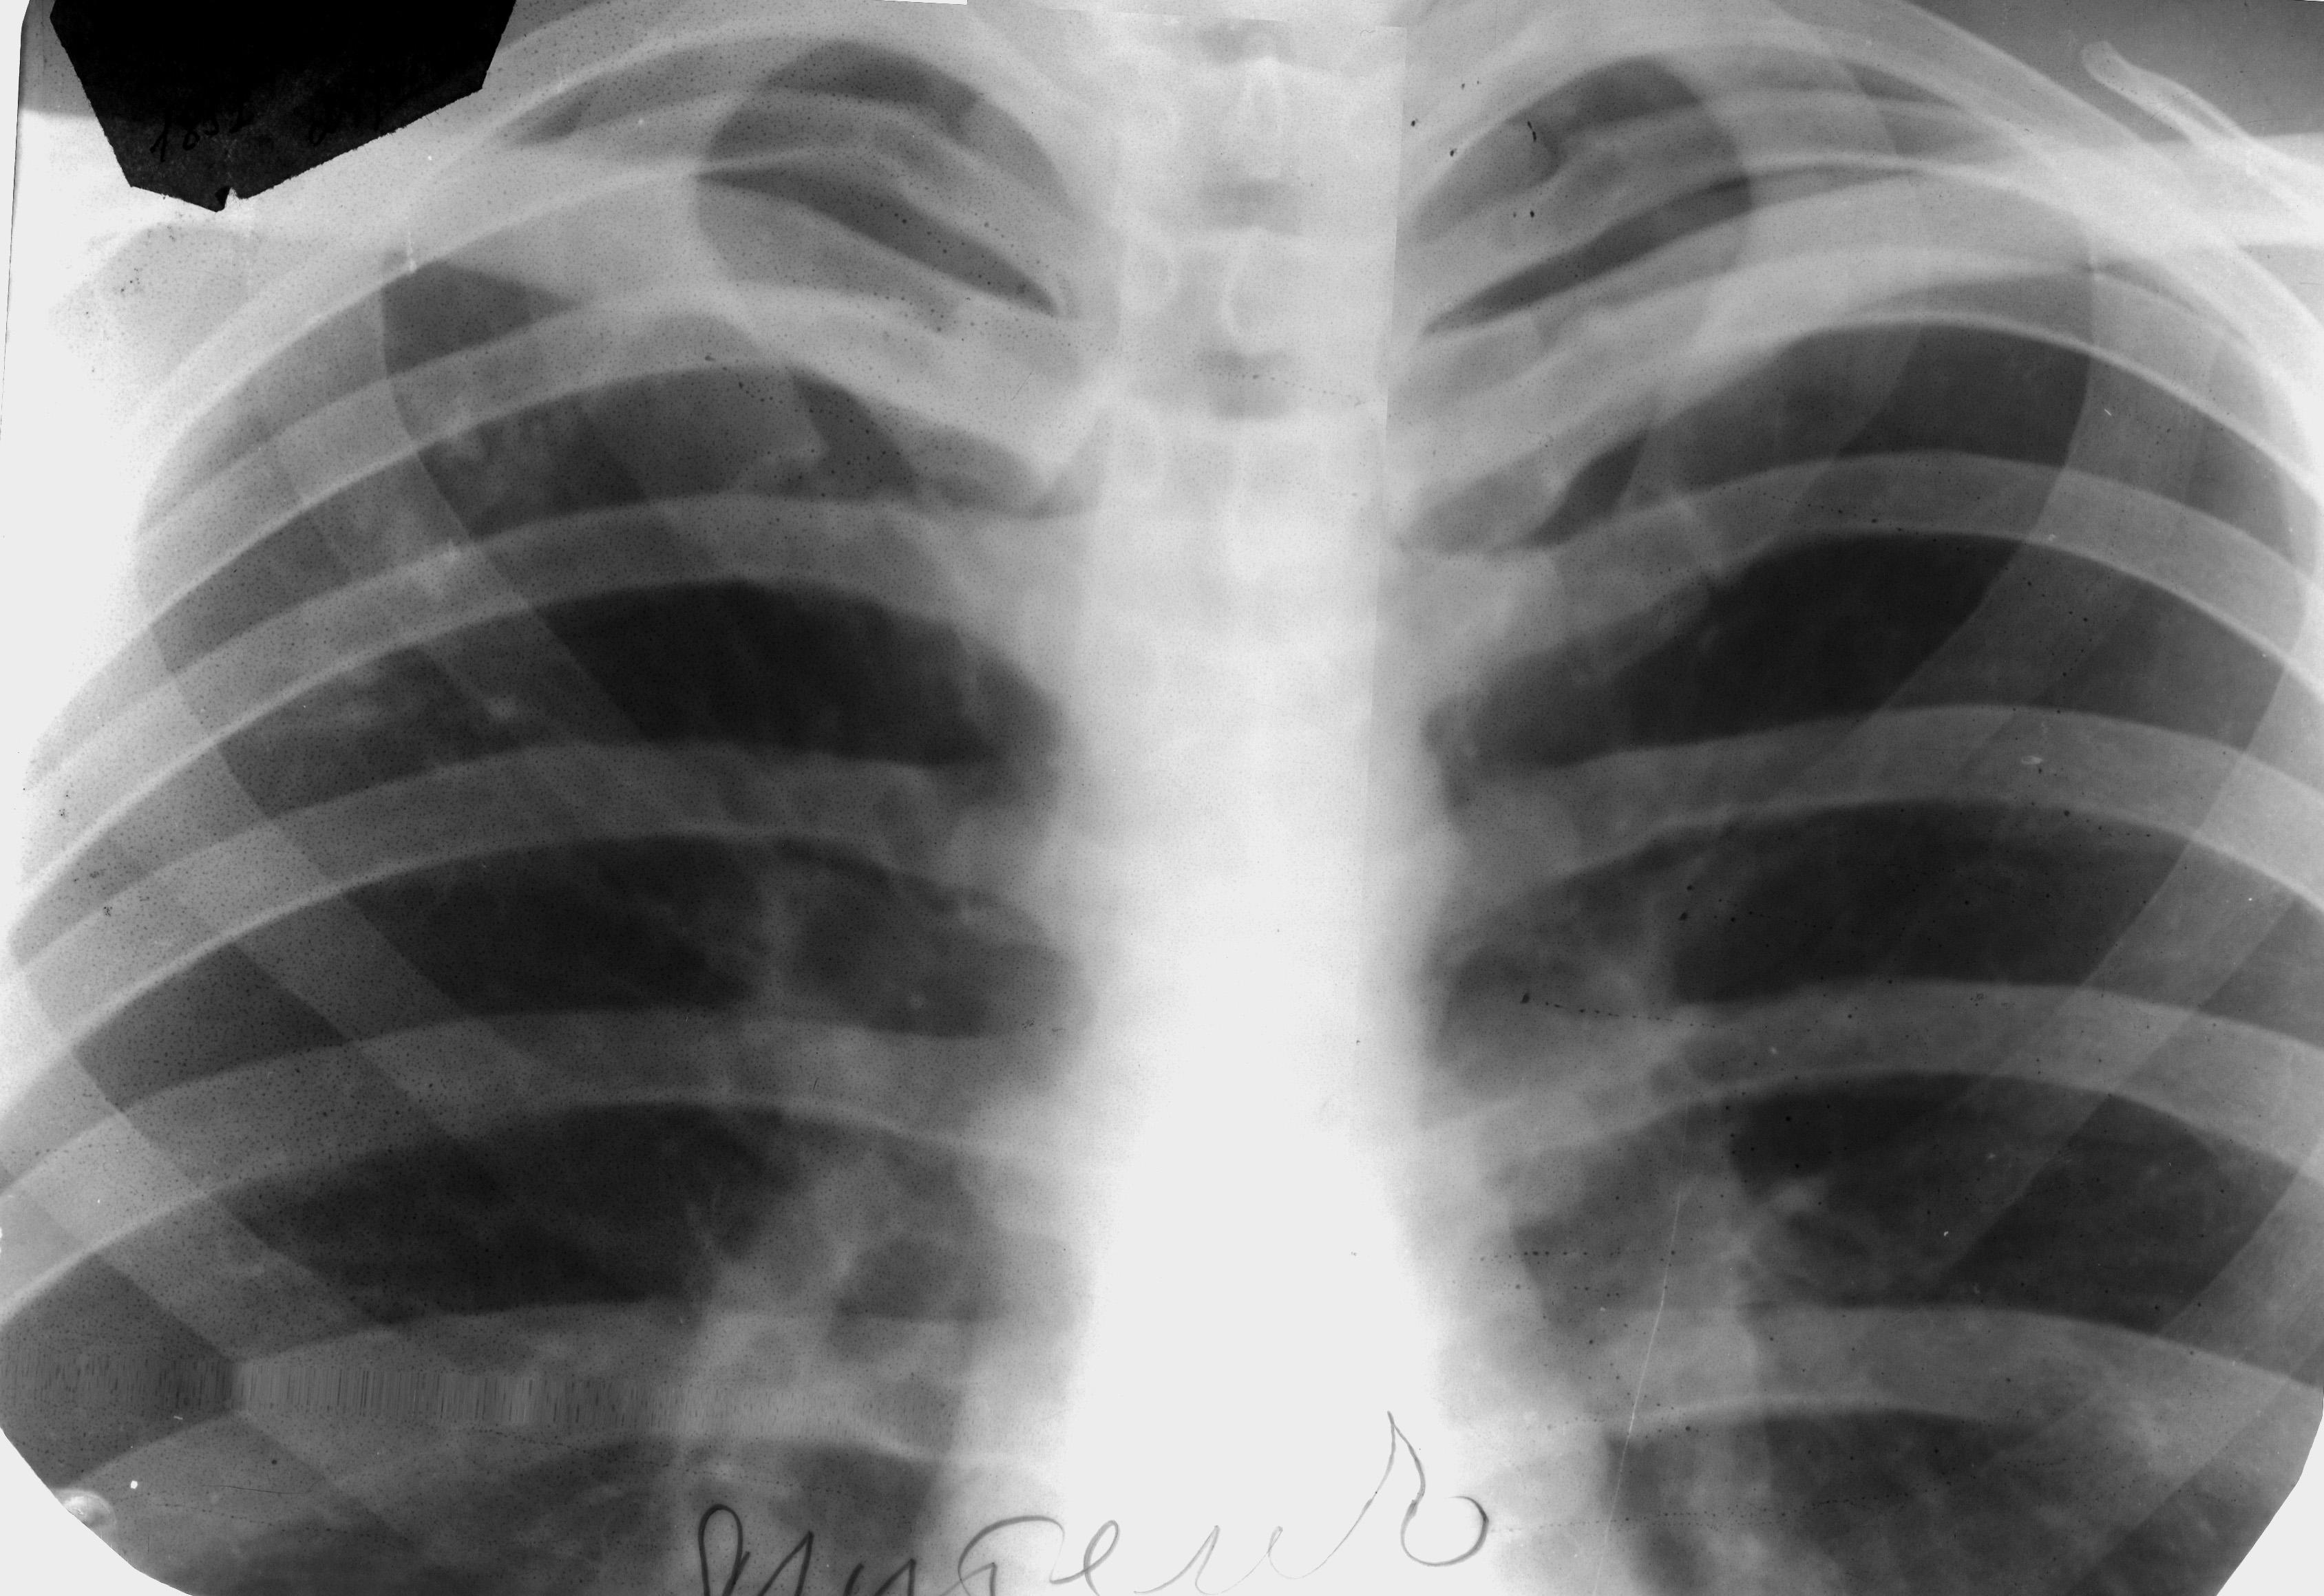

Изучение дозы излучения при рентгеновских исследованиях: визуализация

Раздел: Фотодневник открытий